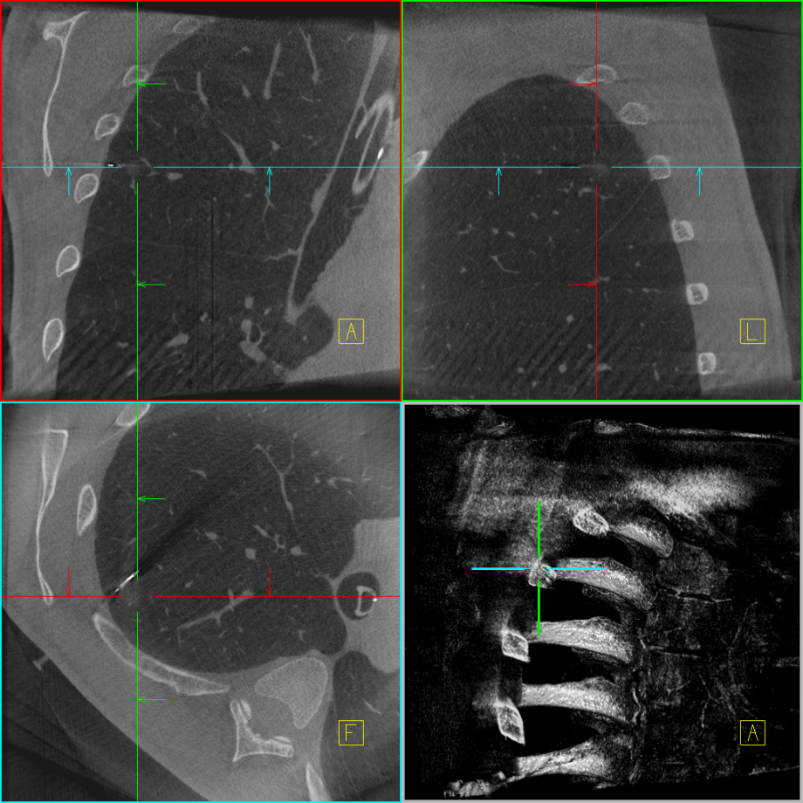

定位前扫描三维

定位后扫描三维

定位针与病灶位置